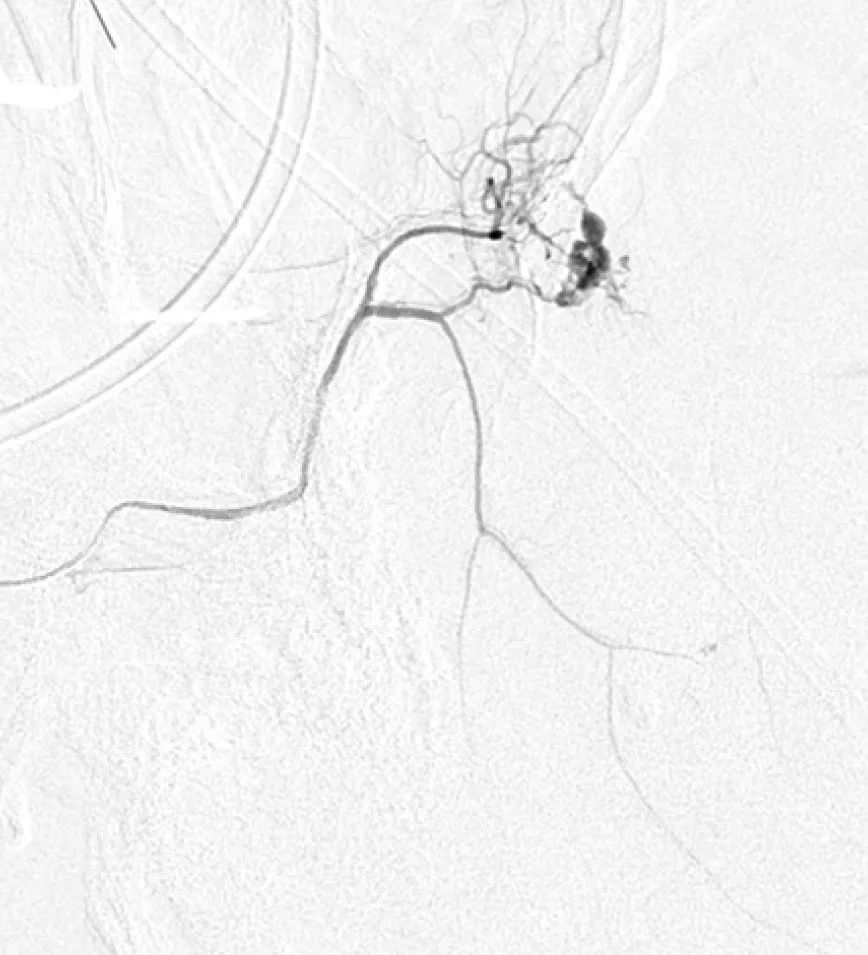

图3,两个病例显示MMA造影剂渗出:

4.jpg